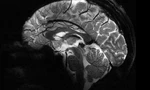

Thông tin đầu tiên được đưa vào trí nhớ ngắn hạn, nơi nó có thể được lưu trữ trong khoảng thời gian từ vài giây đến vài phút. Sau đó, nó được chuyển đến trí nhớ dài hạn thông qua các khu vực như vùng hải mã và cuối cùng đến một số vùng lưu trữ trên não.

Nếu hai nơ-ron thần kinh giao tiếp liên tục, hiệu quả giao tiếp giữa chúng tăng lên. Quá trình này, được gọi là điện thế dài hạn, được coi là một cơ chế giúp ký ức được lưu trữ lâu dài, nhưng làm thế nào một số ký ức lại bị mất đi?

Tuổi tác là một yếu tố. Vùng hải mã mất đi 5% số tế bào thần kinh mỗi thập kỷ và tổng số mất đi là 20% khi bạn 80 tuổi, dẫn đến sự sụt giảm sản xuất chất dẫn truyền thần kinh, như acetylcholine, chất rất quan trọng đối với việc học tập và trí nhớ. Những thay đổi này dường như ảnh hưởng đến cách mọi người truy xuất thông tin được lưu trữ.